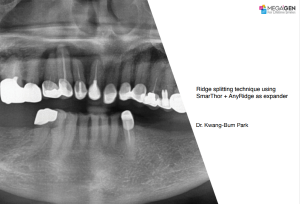

1 34 35 36